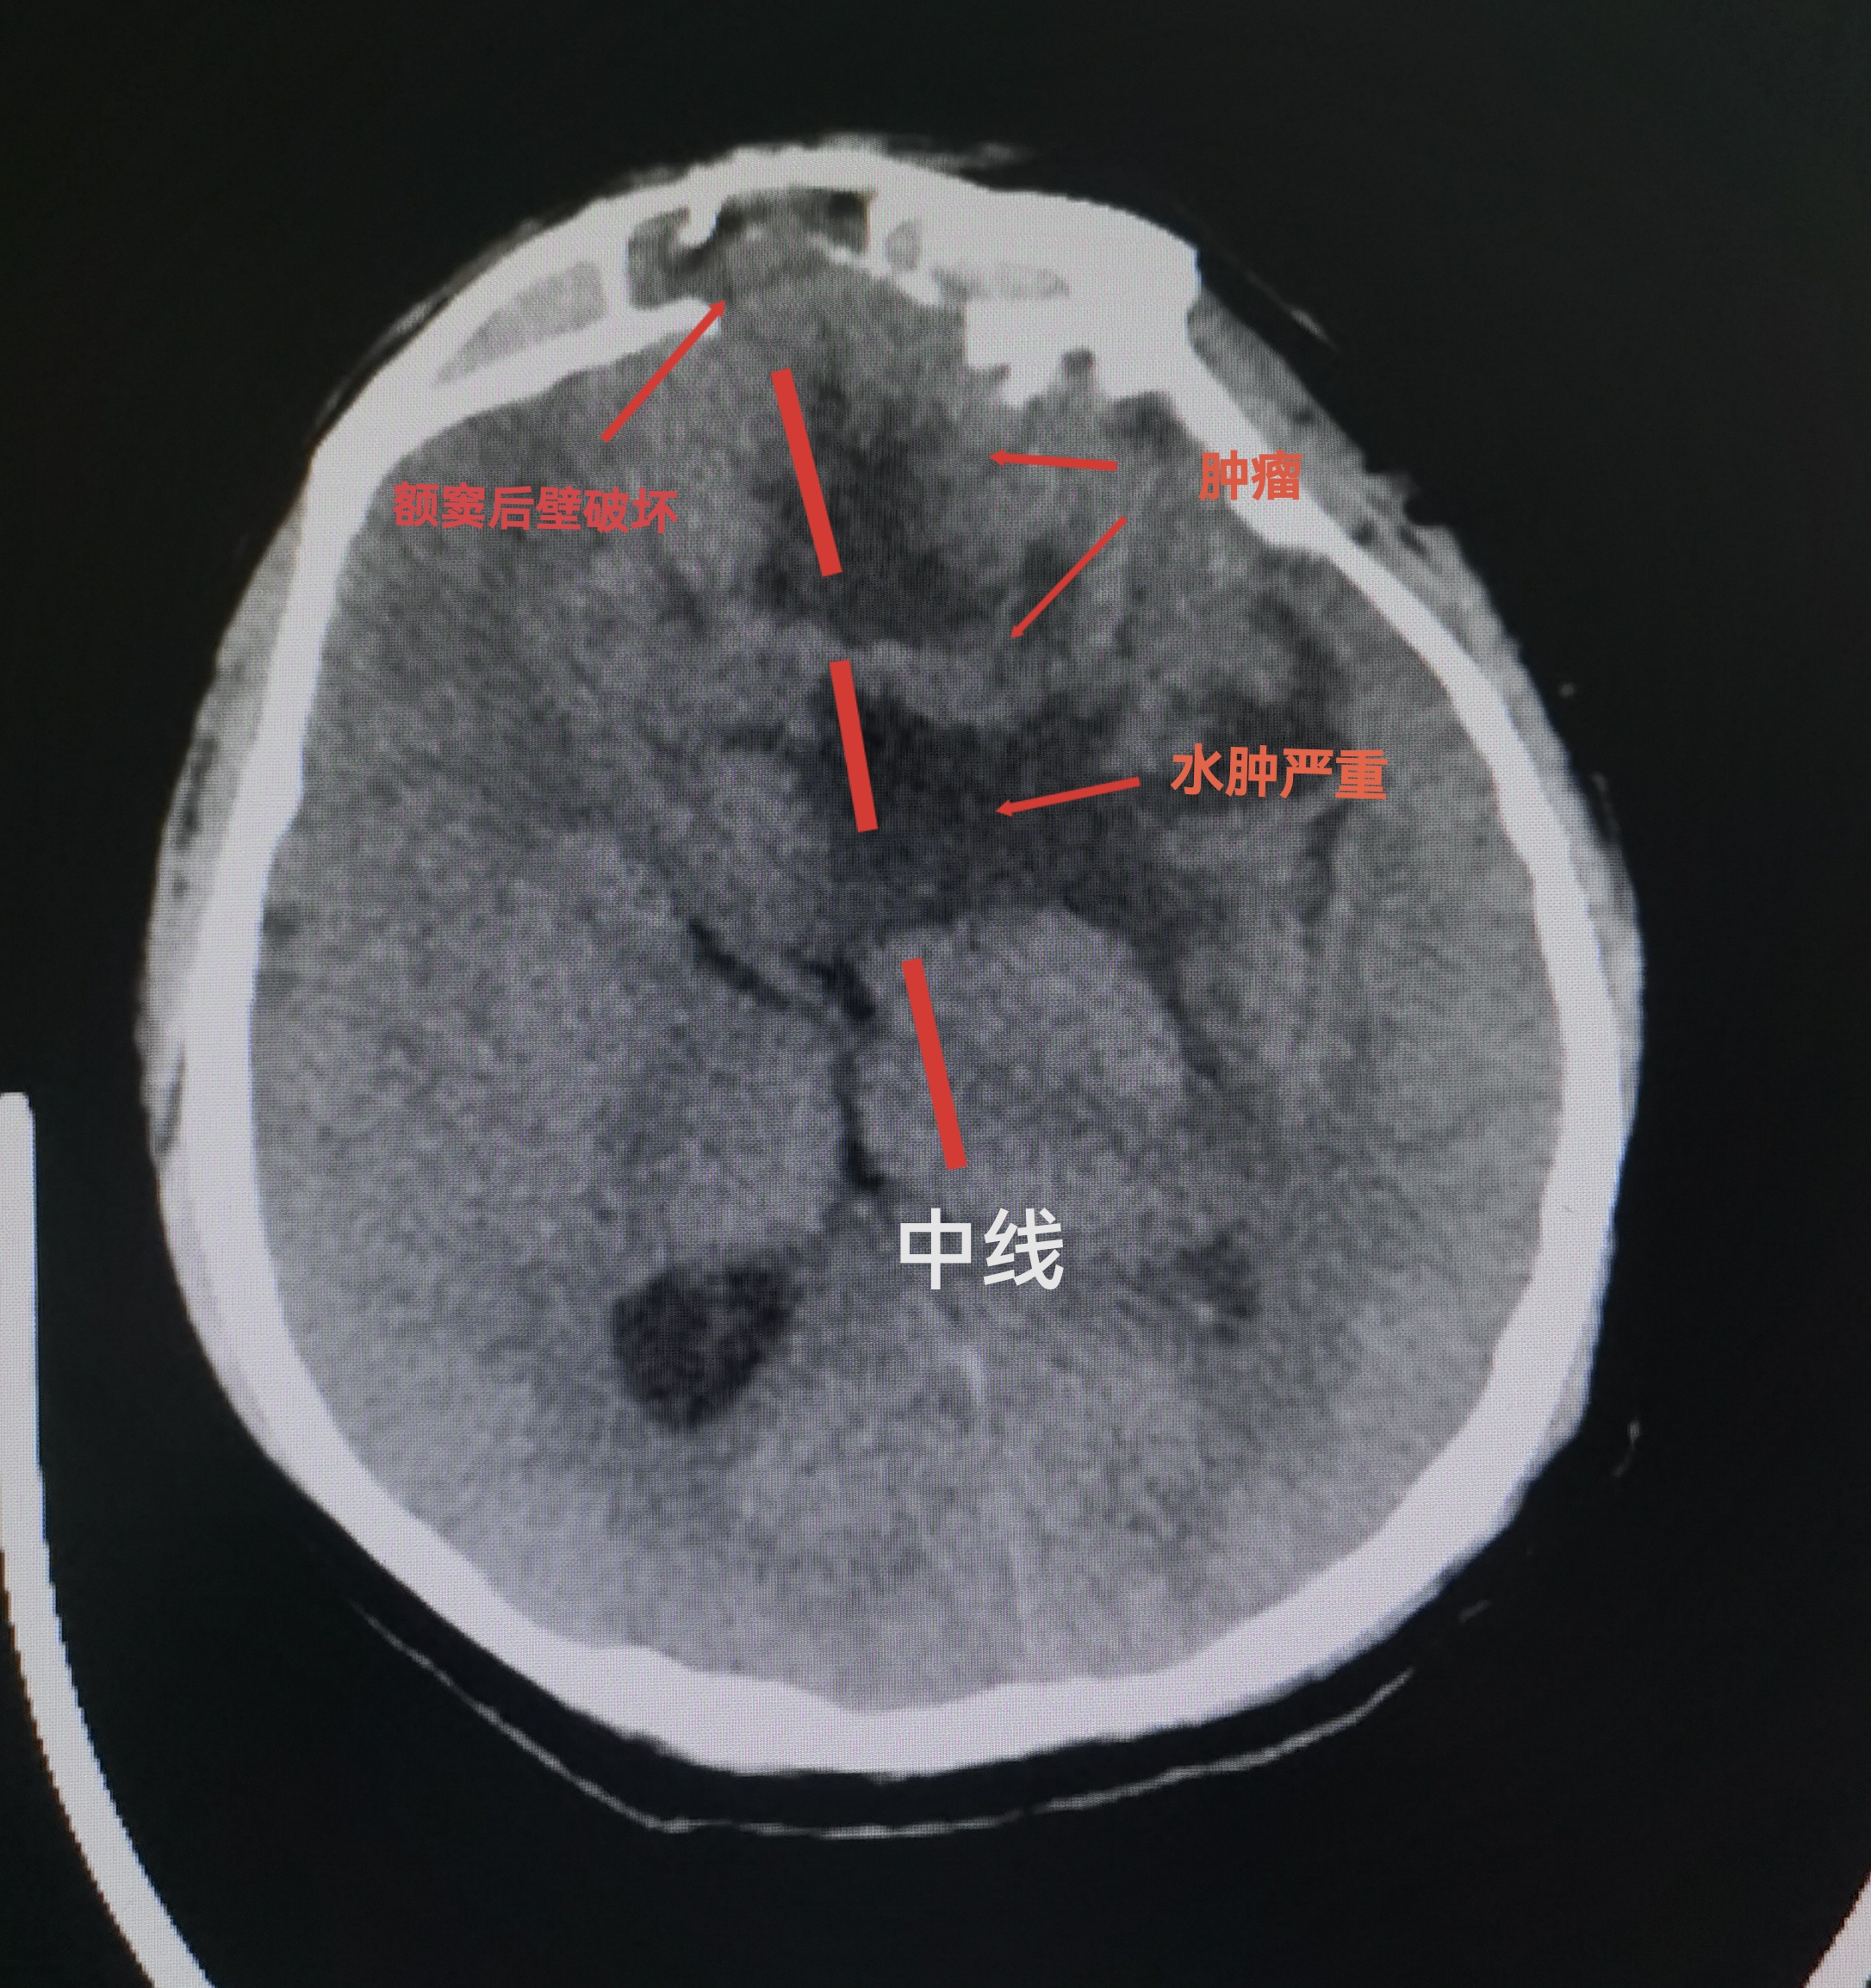

CT扫描可见颅内等密度占位,局部水肿明显,中线向右偏移。冠状位重建可见嗅沟蝶骨平台处骨质破坏导致缺损。

CT提示颅内肿瘤,前颅底等密度为主。周边水肿明显。占位效应造成中线移位。

CT与增强MRI的对比